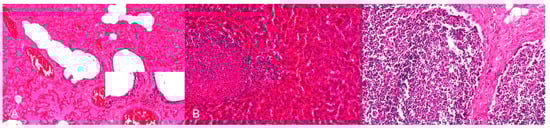

PRV is pantropic which becomes obvious microscopically. Epitheliotropic lesions appear mainly in young or aborted piglets. Multifocal necrosis occurs in the liver, spleen, tonsil, lymph node, nose, lung, adrenal gland, placenta, testicle, stomach and intestine, and is often accompanied by variable numbers of amphophilic intranuclear inclusion bodies [28,38,43,44,47,52]. Hemorrhages can be present in the lymph node [28]. In some cases of naturally infected wild boar and domestic pigs either depletion or hyperplasia of lymphoid tissue is described [28,36]. Lung lesions can be either mild or severe and range from edema to interstitial pneumonia with necrosis of the epithelium, endothelium and connective tissue [34,43,47] (Figure 3). A necrotizing inflammation of arteries, veins and lymphatic vessels accompanied by thrombosis has been described after natural infection [28,38].

Figure 3.

Interstitial pneumonia of a pig after natural PRV infection. The alveolar septa are slightly thickened with lymphohistiocytic infiltration. H.E. (Courtesy: Institute of Veterinary Pathology, Leipzig University, Leipzig).

Neurotropic changes are seen in the brain, spinal cord as well as in spinal and vegetative ganglia as nonsuppurative, mainly lymphohistiocytic inflammation. The inflammatory response is characterized by neuronal necrosis and degeneration, neuronophagia and satellitosis as well as microglial activation and proliferation. Perivascular cuffs consisting of mainly lymphocytes, macrophages, and fewer neutrophils as well as meningeal infiltration are characteristic [44,46,48] (Figure 4). In piglets, panencephalitis is commonly present affecting the brainstem, cerebellum, thalamus and cerebrum including the olfactory bulb [28,44,46,48,52]. Principally, lesions are located in the grey matter, but can also involve the white matter [47,48]. Ganglioneuritis of the trigeminal, spinal, myenteric, submucous and mesenteric ganglia is common [28,43,47,52].

Figure 4.

Nonsuppurative meningoencephalitis in a PRV experimentally infected piglet. (A) Perivascular cuffs consisting of lymphocytes and histiocytes and mild microgliosis (inset). (B) Lymphohistiocytic infiltration of the adjacent meninges with few neutrophilic granulocytes, H.E. (Courtesy: Department of Pathology, University of Veterinary Medicine Hannover, Hannover).